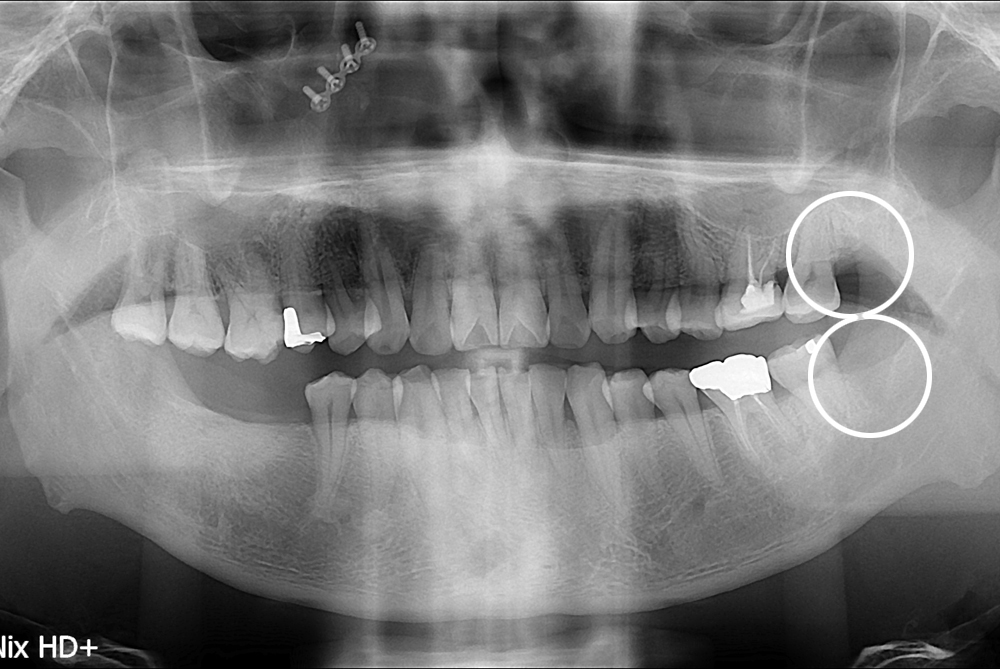

치료후 : 2017-05-17

세종치과는 구강악안면외과학 박사이신 원장님이 발치하는 치과입니다.